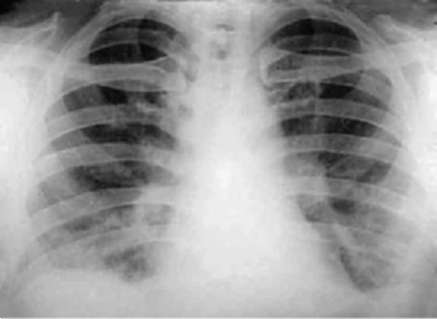

Лучевые методы исследования. Рентгенологическая картина при ЭТА зависит от стадии заболевания. В начальной фазе выявляются признаки отека интерстициальной ткани легких и распространенные мелкоочаговые затенения. При прогрессировании процесса формируются двусторонние изменения легочного рисунка по типу интерстициального фиброза, преимущественно в нижних отделах легких (рис. 2.28). В далеко зашедших случаях определяется мелко- и крупноячеистая деформация легочного рисунка. Описаны случаи, когда единственным рентгенологическим признаком болезни был односторонний плевральный выпот. Отсутствие каких-либо изменений на рентгенограммах отнюдь не исключает ЭТА. Так, при бериллиозе у 23-59% больных может выявляться умеренно выраженная двусторонняя лимфоаденопатия, а в ряде случаев - рентгенотрицательная форма бериллиоза (Dweik R.A., 2015). У 30% из 71 больных ЭТА, наблюдавшихся нами в клинике пульмонологии, в момент обследования изменений на рентгенограммах не было (Орлова Г.П., 2019). Группа больных ЭТА была обозначена условно как рентгенотрицательная группа. Уточнить диагноз помогает КТ легких, выявляющая интерстициальные изменения в легочной ткани по типу «матового стекла», усиление и деформацию легочного и сосудистого рисунка (рис. 2.29), фиброзные изменения тяжистого и звездчатого типов, на поздних стадиях - «сотовое легкое». ВРКТ выявляет «матовое стекло» и другие изменения в легочной паренхиме, которые не видны при обычном рентгенологическом исследовании. Но даже ВРКТ не всегда выявляет изменения в легочной ткани. Так, в 25% случаев гистологически подтвержденного хронического берил-лиоза легких ВРКТ была нормальной (Dweik R.A., 2013; Амосов В.И., Сперанская А.А., 2015; Amanullah S. et al., 2015).

Рентгенологические изменения в легких при ингаляционных лихорадках также могут отсутствовать или проявляться в виде летучих инфильтратов (Ahsan S.A. et al., 2009; Shimizu T. et al., 2012; Greenberg M.I. et al., 2015). При бериллиозе, помимо диффузных инфильтратов и усиления легочного рисунка, за счет интерстициального компонента у 23-59% больных может выявляться лимфаденопатия (Sirajuddin A. et al., 2009).